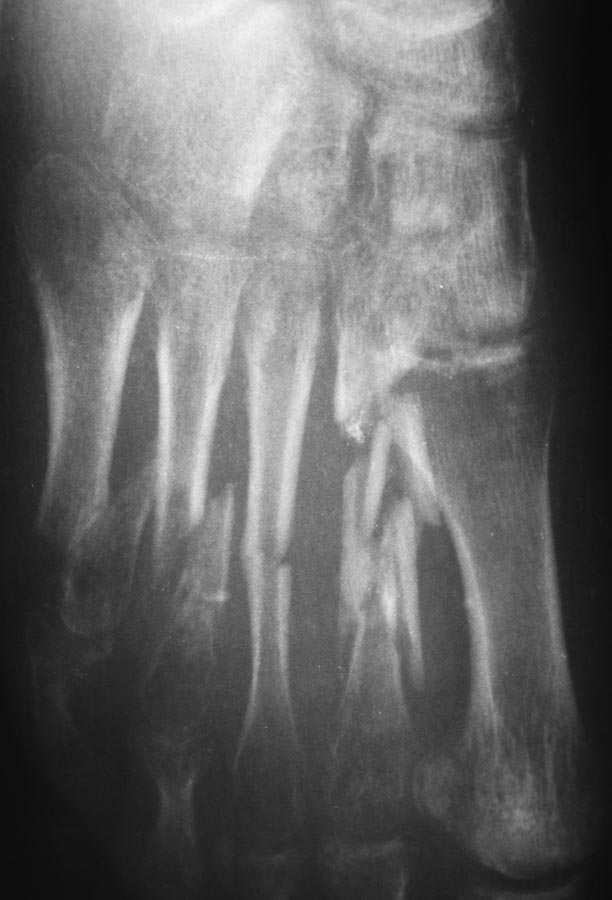

Пациентка 19 лет 11.05.13 получила травму в результате ДТП. диагноз:

Открытые 3а степени оскольчатые переломы диафиза 2-5 плюсневых костей,

перелом проксимальной фаланги 5 пальца, разрыв сухожилия разгибателя 4

пальца правой стопы. При поступлении выполнено ПХО открытых переломов,

фиксация спицами. Рана тыла стопы заживала без воспаления, однако

имелся частичный некроз кожного лоскута. По снятии швов произведена

иммобилизация циркулярной повязкой. Снимки стопы через 2,5 мес.

иммобилизации.